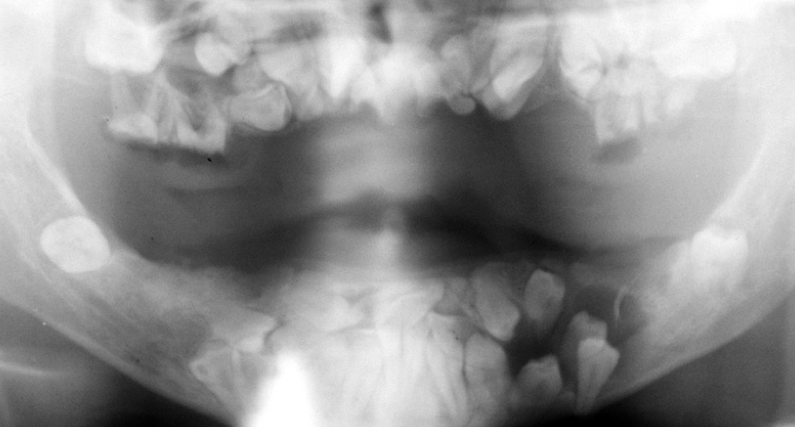

What is the likely Dx?

Osteopetrosis.